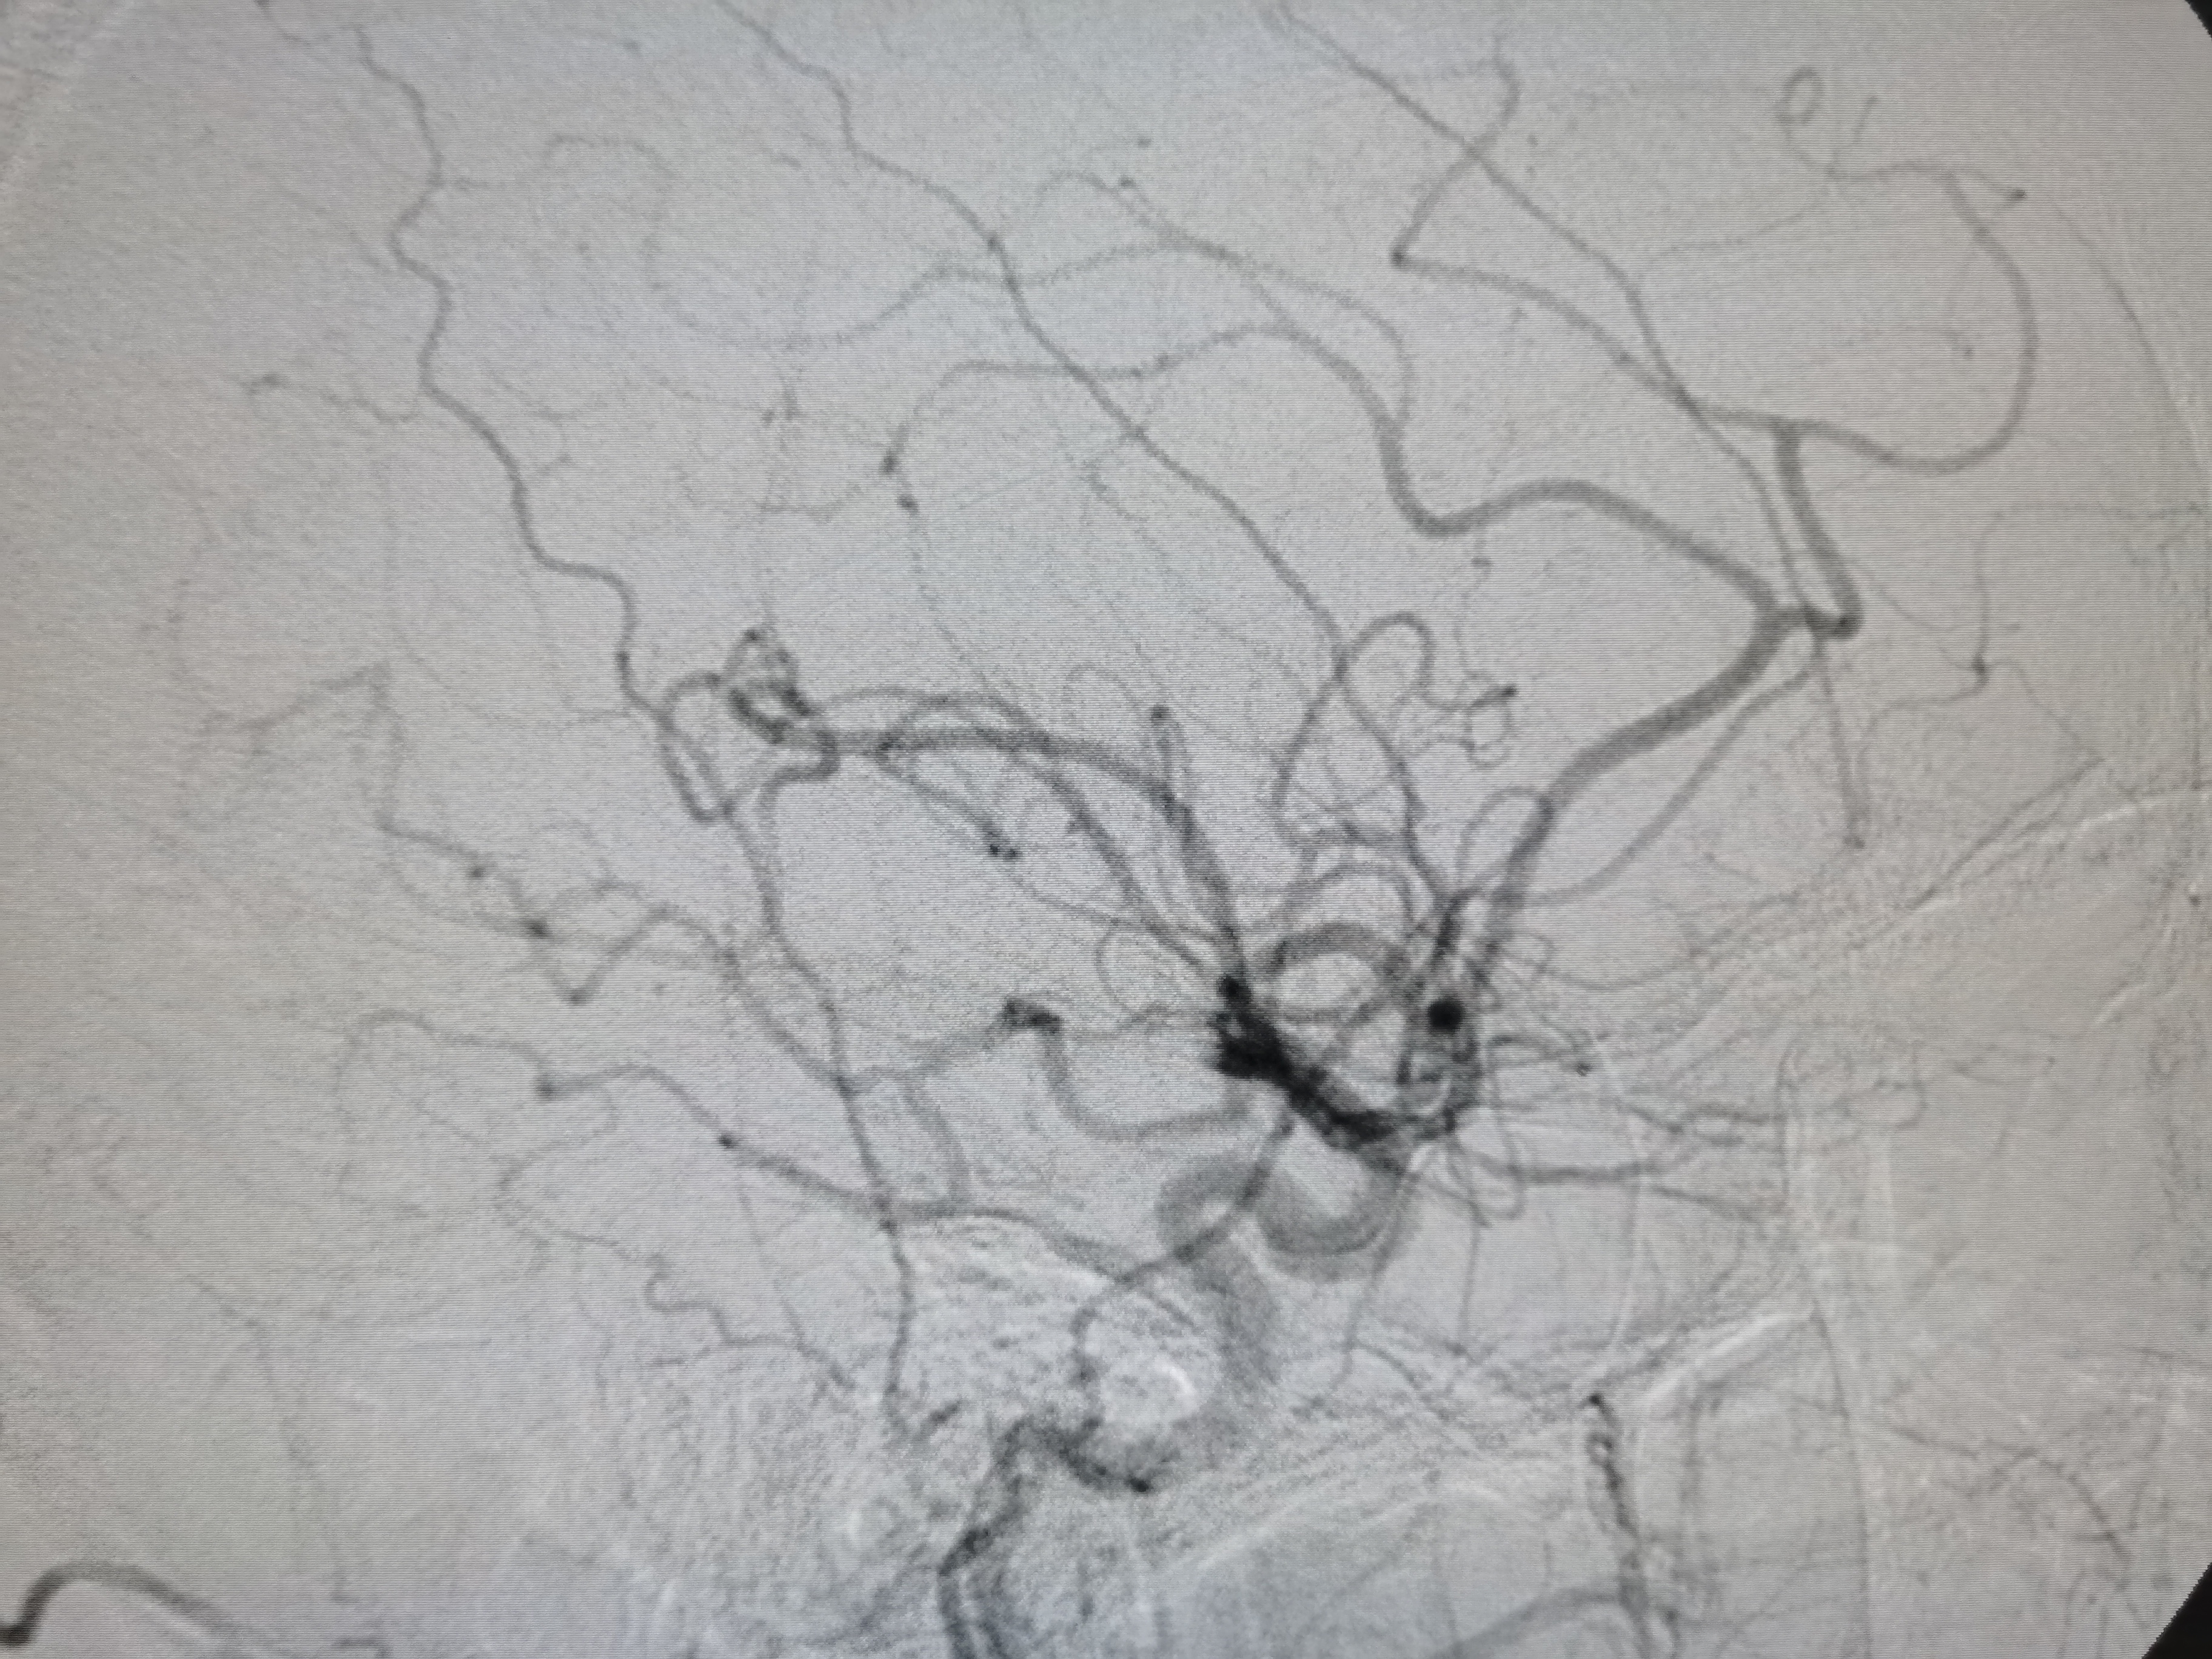

将8F导引导管送至左侧锁骨下动脉近左椎动脉起始部,微导丝顺利通过病变,2.0/20球囊预扩病变。

3、手术过程中,先用小球囊扩张病变,观察血栓情况,及时应用支架全程覆盖血栓及病变部位,成形满意。